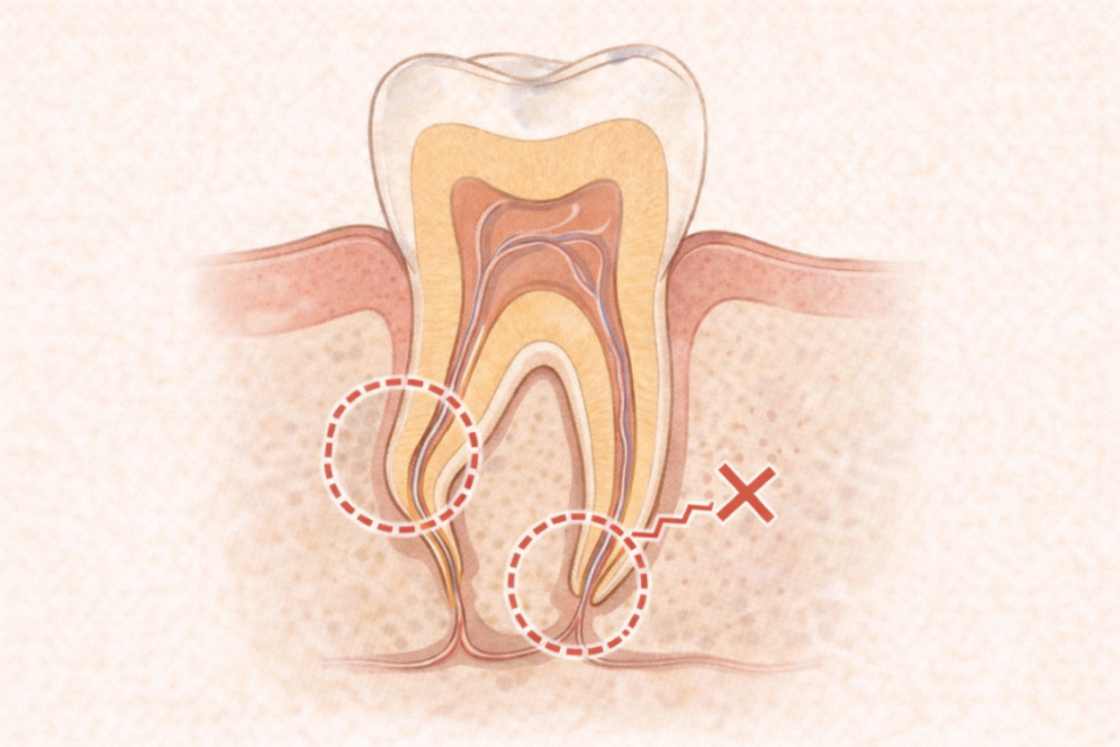

① 根の形が複雑

歯の根は、見た目以上に細かく曲がりくねっています。

特に奥歯は根が3〜4本あり、それぞれに枝分かれした細い管(側枝)があるため、器具が届きにくく時間がかかります。

② 根管が“根詰まり”している

以前の治療で入った薬剤が硬く詰まっていたり、器具の破折、変形などがあると、

新しく器具を入れるまでに時間がかかります。

いわゆる 「再治療の歯」 は、初回よりも治療が難しく、慎重な作業が必要です。